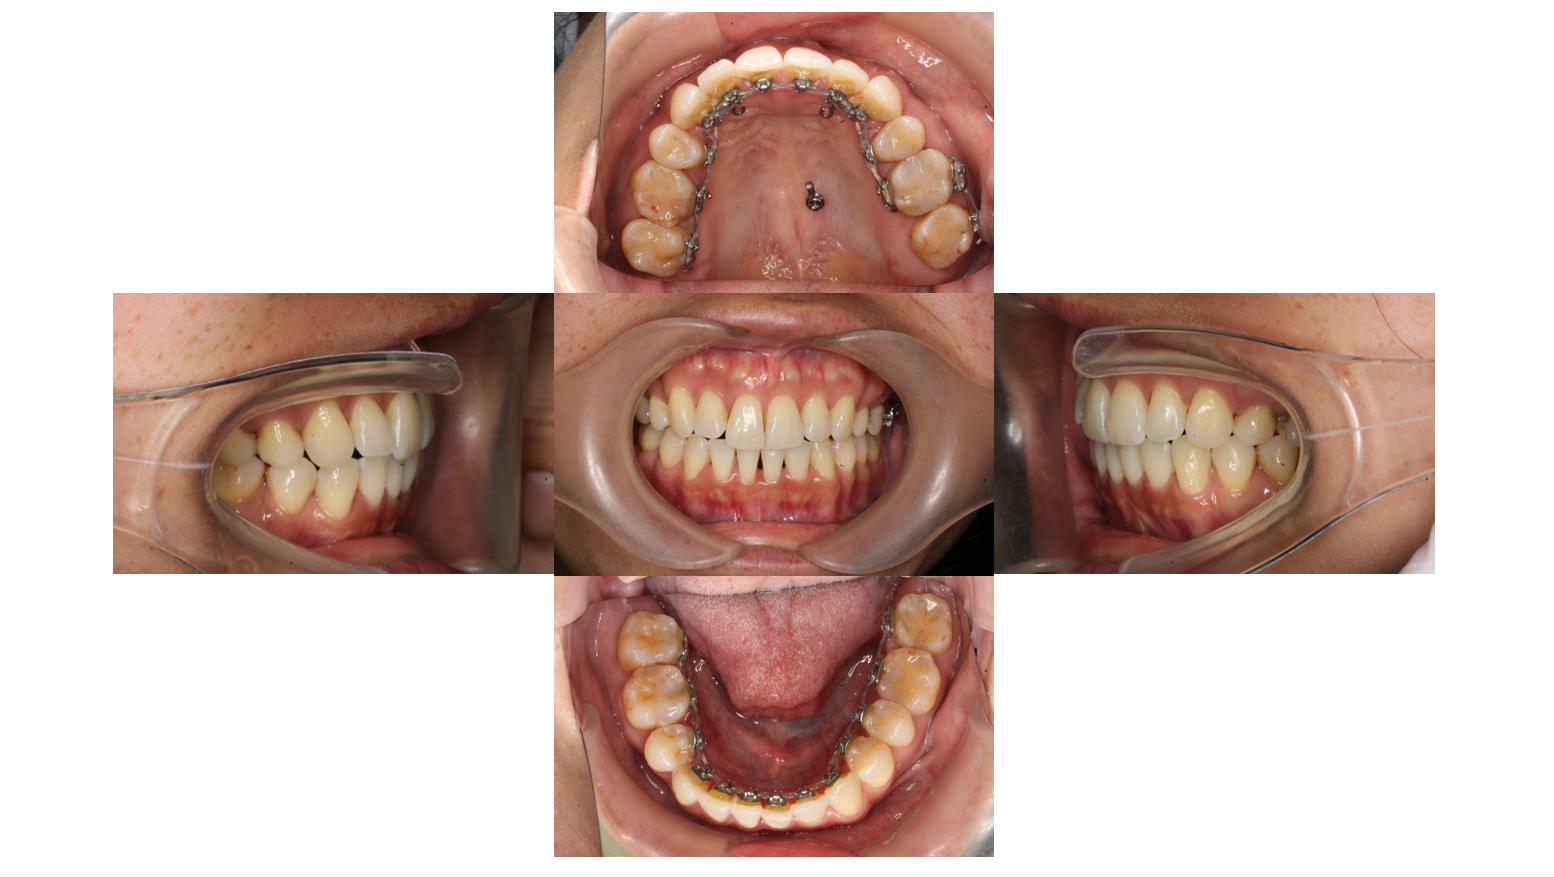

After

2年経過

フックからねじでゴムかけをして前歯を後ろに下げます

2年11か月経過

全体的に装置にゴムかけをして歯に隙間が空いてこないように調整します